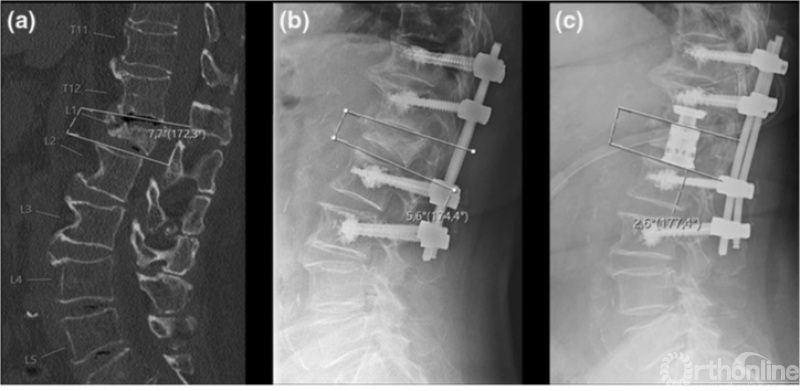

Maximilian等[9]对OVCF患者应用人工椎体置换术与单纯后路螺钉固定治疗效果进行比较,认为360°固定融合术是一种合理的手术方式,即使对于老年人和骨质疏松人群,也不会增加并发症的发病率。